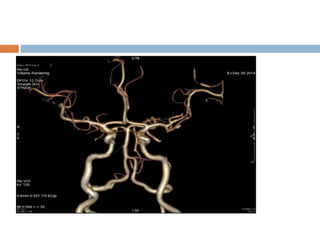

Neuro – imaging

 CT and CTA

 MRI – MRA

aetiology investigtion

 Echo –cardiography.

 Extra and intracranial duplex.

 CTA & MRA.